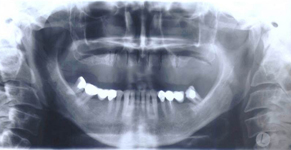

Augmentační postupy jsou zákroky minimálně invazivní až po náročnější operace upravující nedostatečnou nabídku alveolární kosti co do kvantity a kvality.

Tyto postupy nám umožní doplnit chybějící množství kosti v čelistech pacienta i zlepšit kvalitu kosti. Většinou se setkáváme s omezenou nabídkou kostní tkáně díky resorpčním (úbytkovým) procesům způsobených věkem či vytržením zubu, přítomností anatomických struktur jako je čelistní dutina, nervový kanál nebo patologických či poúrazových stavů - cysty, zlomeniny.

V těchto případech musíme použít některou z následujících pomocných metod:

Při ztrátě molárů a premolárů v horní čelisti a jejich náhradě implantáty se často setkáváme s nedostatečnou vertikální nabídkou kosti pod čelistní dutinou, často doprovázenou i nedostatečnou horizontální nabídkou a sníženou kvalitou kosti

(v oblasti 2. premoláru v 50%, v oblasti moláru až v 80% případů nedostatečná kostní nabídka)